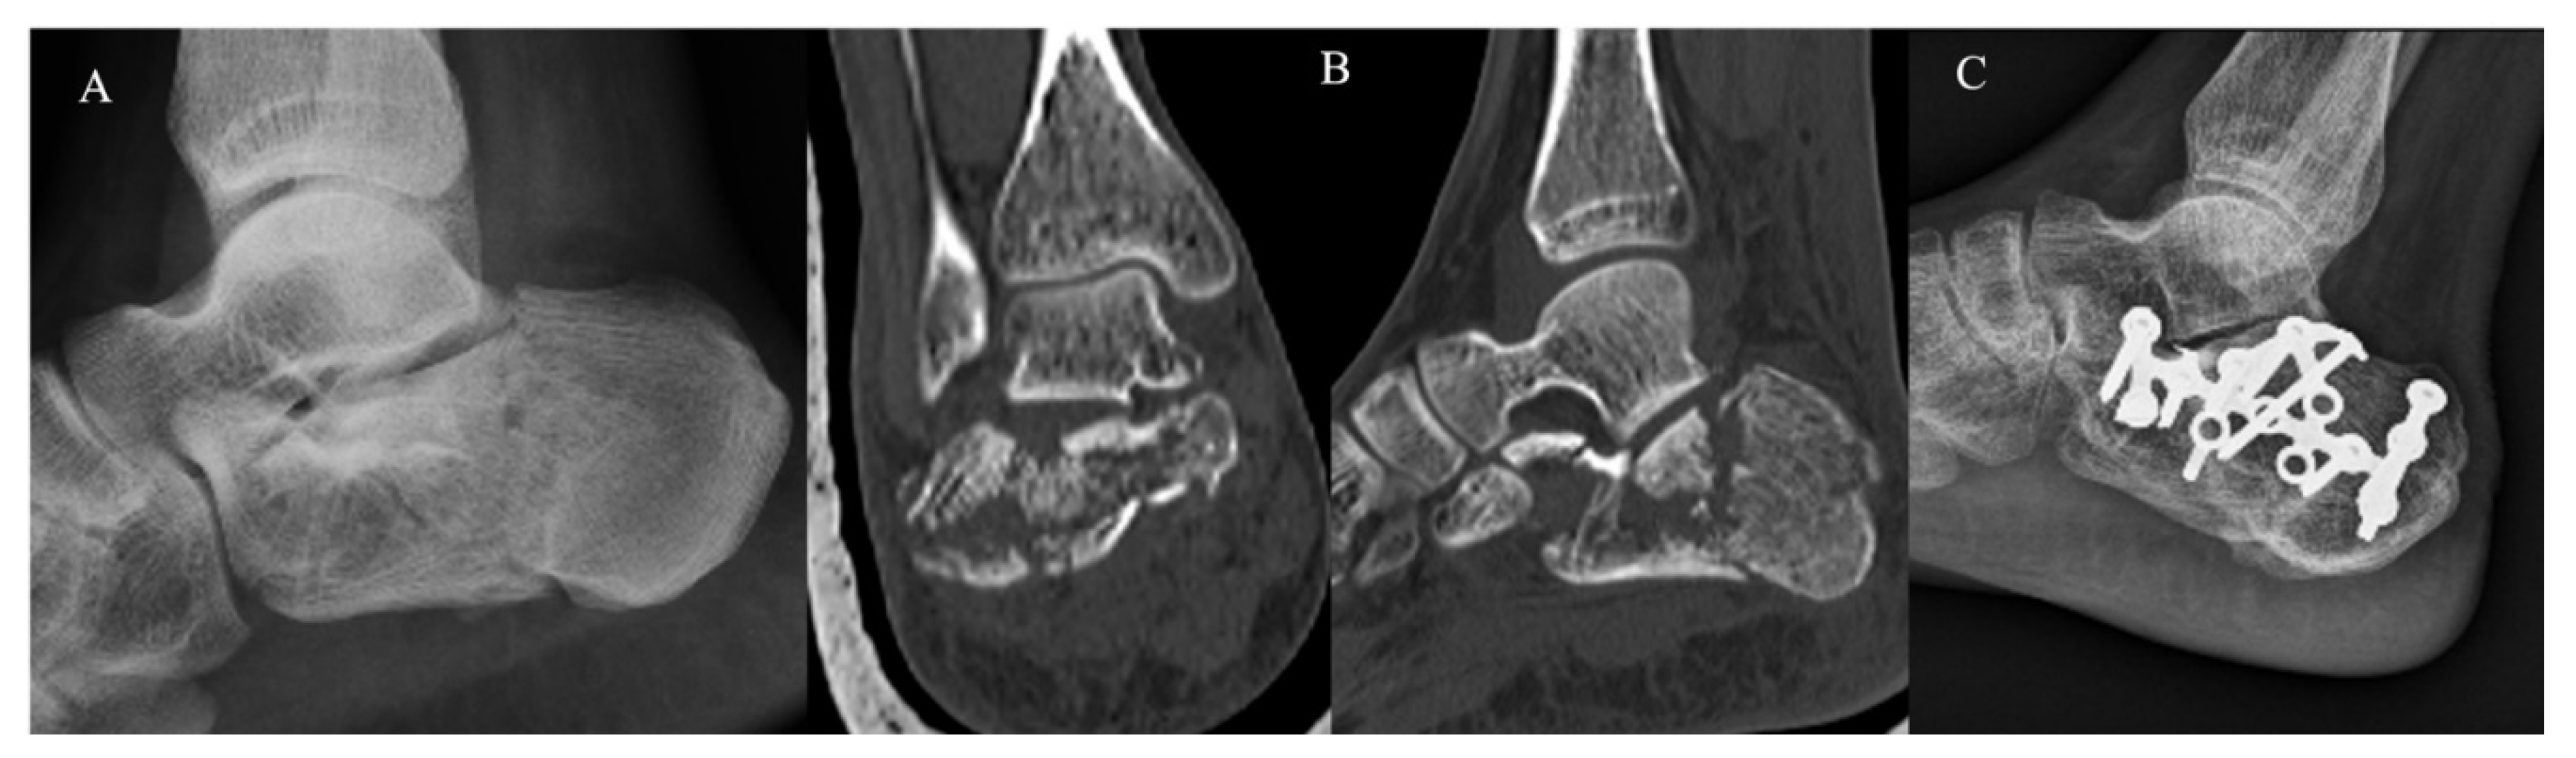

The KG (Figure 2) and PG (Figure 3) consisted of 20 and 22 CF, respectively. The group demographic characteristics and specific mean final follow-up are summarized in Table 1.

Figure 3.

Extended approach and dedicated plate. (A) Pre-operative radiographs; (B) pre-operative CT scan in coronal and sagittal plane showing a Sanders III CF; (C) post-operative radiographs at 4-year follow-up.

At the final follow-up of 62.5 ± 16.3 months, the PG (50% of the entire pool) showed a mean post-operative AOFAS score at the end of follow-up of 70.1 ± 10.9 (46–85), a mean SF-12 PCS score at the end of follow-up of 46.5 ± 10.8 (28.9–58), and an SF-12 MCS score of 50.9 ± 11.8 (24.3–68.6). Nine patients (47.3%) underwent subsequent re-interventions, which, in all cases, involved removal of the hardware, due in six patients to intolerance (31.5%), and in three patients due to post-operative infection of the dedicated plate (15.7%). Finally, one patient underwent two reoperations, one year post-operatively to remove the hardware and two years later to perform a subtalar arthrodesis for severe post-traumatic osteoarthritis. The complications recorded in the PG (11, for a total of 57.8%) reflect almost exactly the number and type of re-interventions (six due to hardware intolerance, three post-operative local infections, two post-traumatic osteoarthritis).